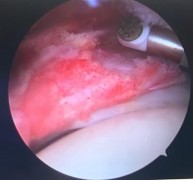

- Làm sạch và đốt tổ chức viêm.

Hình 2.18. Đốt tổ chức viêm trong khoang dưới MCV

* Nguồn: ảnh chụp trong mổ của BN Nguyễn Văn Ph, mã số bệnh án 2002240716